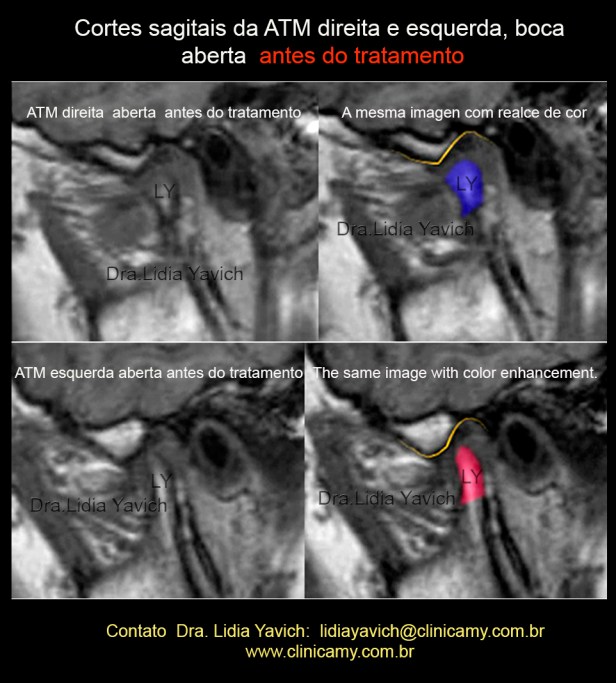

RNM TI: Um corte sagital da ATM esquerda e da ATM direita em boca aberta.

Podemos observar facetas anteriores nas cabeças mandibulares tanto do lado direito como esquerdo. Ambos os côndilos mandibulares não conseguem transladar estando diminuída a abertura bucal.